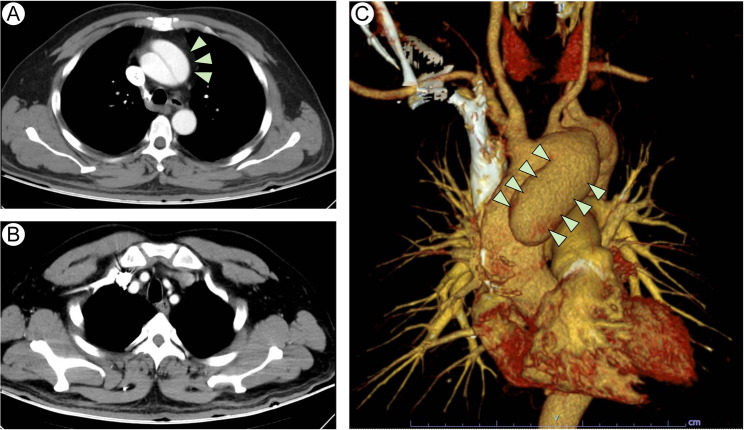

Methods: A 46-year-old male presented to a rehabilitation center with migrating right shoulder pain and proximal weakness. Initial complaint suggested a musculoskeletal disorder; however, further evaluation revealed hypertension, tachycardia, and migratory, intensifying pain. A subsequent computed tomography angiography confirmed AAD. The patient underwent urgent Sun's procedure, including ascending aorta and total arch replacement with stented elephant trunk implantation, which was followed by multidisciplinary rehabilitation due to the secondary ischemic stroke.